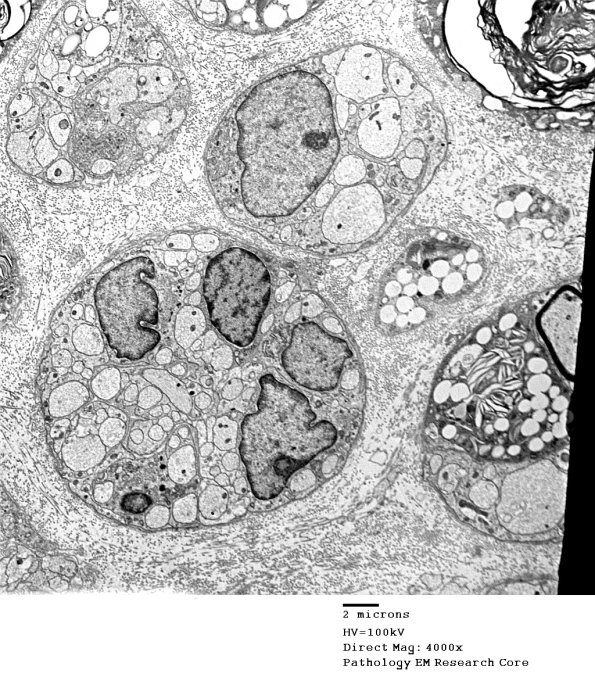

Various combinations of regenerating axons and continuing macrophage reaction. (Electron micrograph)